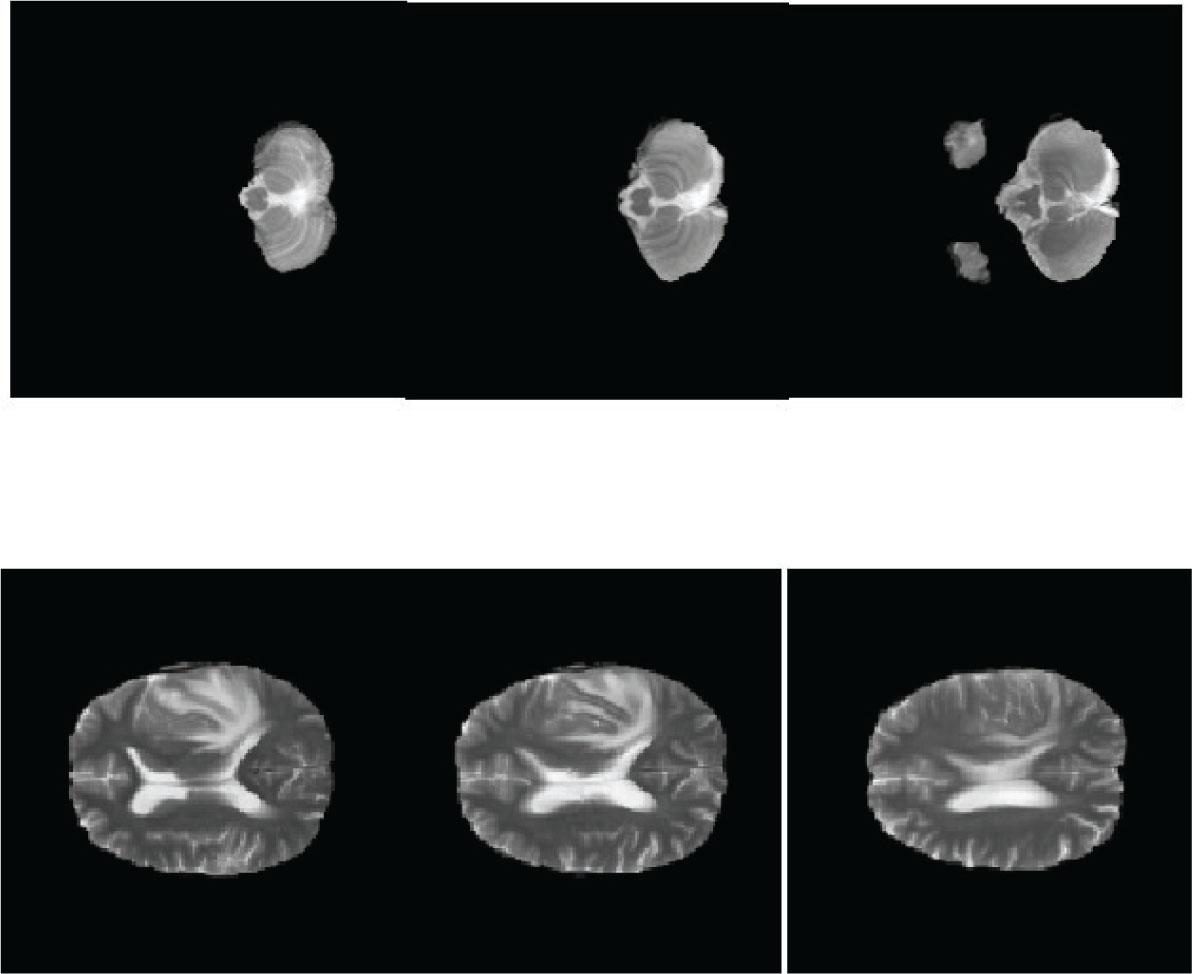

We calculated the accuracy and computation time after every small set of features was obtained. The best accuracy was obtained after 35 features. The method yielded saturated results after accommodating 35 features out of a total of 42 features gained. These features were in the fused format after applying the PLS method (Figures 7 and 8). Thus, accuracy can be achieved even with fewer fused features (Figure 9). These results were produced with different classifiers, as shown in Table 2. We compared the results when different classifiers, such as SVM, naïve Bayes, SoftMax, and decision tree, were used. The comparison was performed on two sets of datasets, BraTS2018 and BraTS2019, and it was observed that the approach performed better for BraTS2019 than for BraTS2018 (Figure 11). The reason behind this is the format of the data presented to the methodology in accordance with the dataset. Another observation was on behalf of the type of classifier to be used with the LTcP and PLS images.

Feature fusion result after applying PLS for (A) T1 MRI images, (B) T2 MRI images, and (C) FLAIR MRI images. MRI, magnetic resonance imaging; PLS, partial least squares.